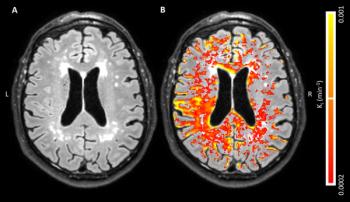

Using MRI to evaluate blood-brain barrier disruption following intracranial hemorrhage may predict severity after intervention.

MRI may help detect Alzheimer’s before directly visible cerebrovascular abnormalities are present.

Adding arterial spin labeling to MRI may help classify and predict Alzheimer’s diagnosis and progression from subjective cognitive decline.